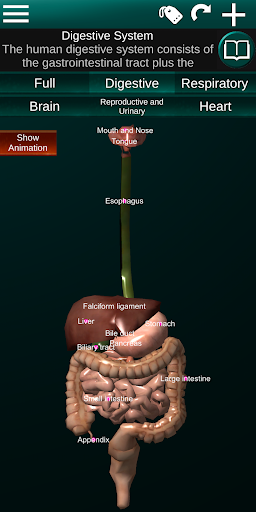

Toont een 3D-anatomisch model van de belangrijkste organen van het menselijk lichaam en een beschrijving van elk orgaan.

* Spijsverteringsstelsel, inclusief de maag, dunne darm, dikke darm, en een animatie van dit systeem.